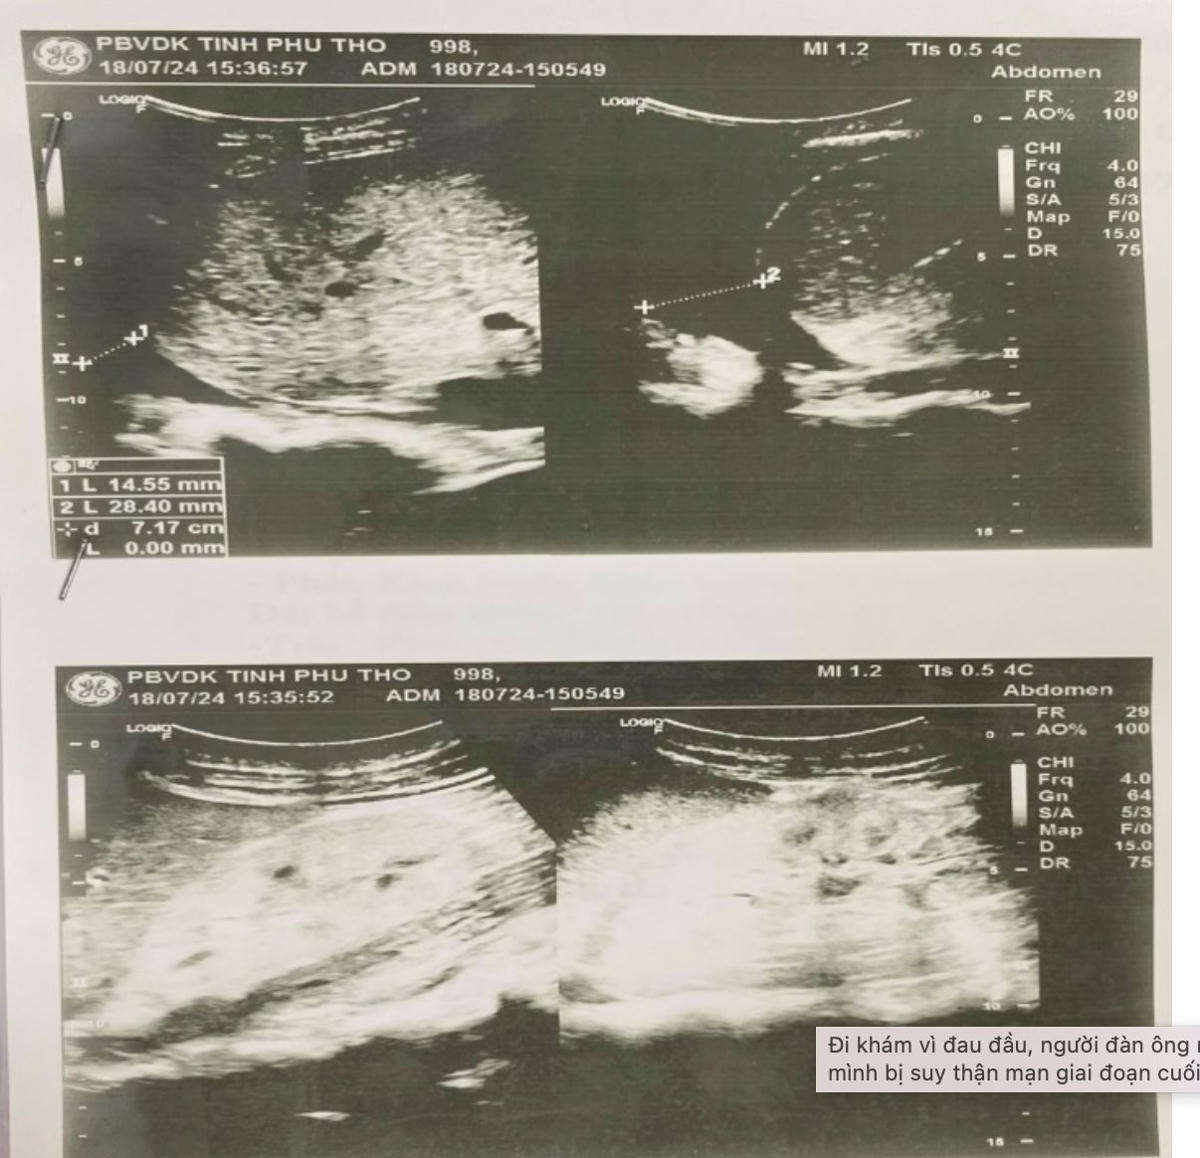

Tại Bệnh viện đa khoa tỉnh Phú Thọ, sau khi khám lâm sàng và làm các xét nghiệm, siêu âm tổng quát đã cho thấy có thiếu máu; huyết áp cao; chức năng thận suy giảm nhiều; trên siêu âm 2 thận đã teo nhỏ, có dịch ổ bụng và dịch màng phổi hai.

Người bệnh được chẩn đoán suy thận mạn giai đoạn cuối/tăng huyết áp, thiếu máu, tràn dịch đa màng, đã được chuyển vào điều trị nội trú.